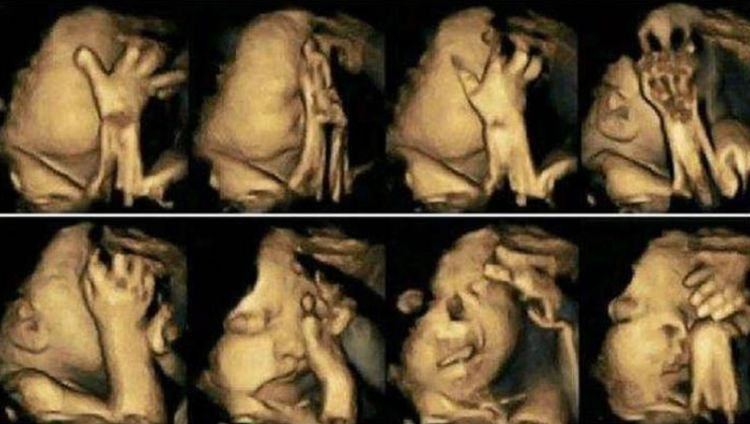

90后,小齐已经怀孕六个多月了。今天,她来医院做了大面积的畸形筛查。通常她常常觉得腹部的婴儿特别活泼动人,整天都在肚子里移动。这次例行检查,小琪并不介意,觉得确定没问题。当她进入B加班时,通过电脑屏幕,医生报告说孩子一直在移动,看不到另一半的脸,而小琪却被孩子们在屏幕上的各个位置逗乐了。心理美女认为这个孩子必须聪明,表现如此小,看起来如此可爱。

医生让小齐出去散步,让孩子露脸,然后来看看。小琪跑出去抽烟,进了B超市。医生闻到烟雾,问她是否吸烟。小琪并不在乎说她的朋友在她身边抽烟,不管是否怀孕。此时,屏幕上的孩子被暴露,很明显有唇裂和腭裂。小琪是差异,但医生建议她堕胎。

医生说:如果孩子动了太多,这并不意味着一定是好事。它也可能在胃中不舒服。他经常摇摆着提醒他的母亲,小琪认为这种情况是无形的。他也开始了解孩子的活力,吸烟并未被打破。你认为你是什么样的母亲?现在孩子有身体缺陷,建议家长清楚地思考,如果它出生,肯定会接受大手术,并且不能恢复正常外观。

小琪从未想过,活泼的孩子居然不舒服,自己未能听到孩子的建议,这位年轻的妈妈流下了眼泪。编辑想提醒所有孕妈妈,怀孕一定要注意休息,拒绝不健康的饮食和工作,保护我们的孩子。照片来自互联网。如果有侵权,请联系作者